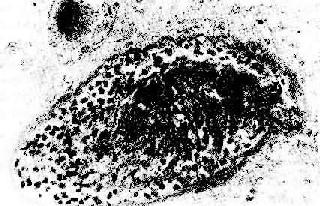

图4-6 肾移植急性排斥反应 肾肿胀,明显出血,肾盏及肾盂中充满血块 3.慢性排斥反应 慢性排斥是反复急性排斥的积累,其突出的病变是血管内膜纤维化,常累及小叶间弓形动脉。动脉内膜纤维化引起管腔严重狭窄(图4-7),导致肾缺血,表现为肾小球毛细管袢萎缩、纤维化、玻璃样变,肾小球萎缩,间质除纤维化外尚有中等量单核、淋巴细胞浸润。肉眼观,肾体积明显缩小,并有多少不等的瘢痕(“小瘢痕肾”)。包膜明显增厚并有粘连。患者肾功能呈进行性减退,其程度与间质纤维化和肾小球、肾小管萎缩的程度成正比。

图4-7 肾移植慢性排斥反应 小叶间动脉管壁纤维化,管腔闭塞,内膜有中等量单核细胞浸润,管周组织内也有类似的细胞浸润 4.移植物抗宿主反应 移植物抗宿主反应(graft versus host reaction,GVH)是免疫缺陷患者接受骨髓移植可发生的一种反应,。在此过程中,移植骨髓的部分干细胞分化成T细胞或B细胞,当其与宿主组织HLA相接触时可诱发:①CTL和淋巴因子形成,导致细胞介导免疫反应;②抗宿主HLA抗体形成,导致体液免疫反应,是GVH发生的主要机制。临床上,患者表现发热、体重减轻、剥脱性皮炎、肠吸收不良、肺炎及肝脾肿大等,其中些是由于感染所致。GVH的程度与供体和受体的HLA差别程度有关。本型反应多见于用骨髓移植治疗再生障碍性贫血、造血系统恶性肿瘤,特别是经细胞毒性药物或放射治疗后正常造血细胞和白血病细胞均被消灭的病例。